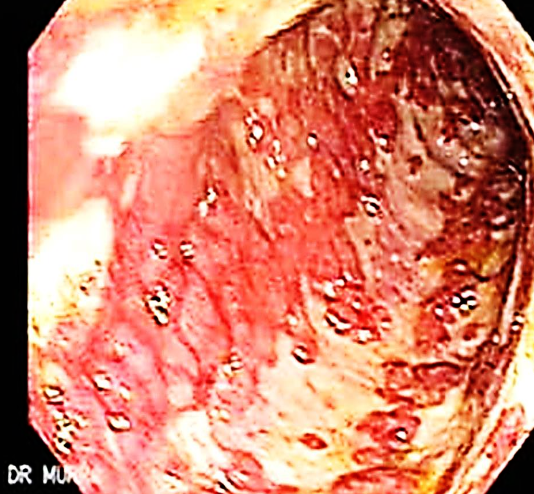

This is an endoscopic image of colon affected by ulcerative colitis. The mucosa is blotchy and broken in many places.

Q1: Name 3 common clinical symptoms of ulcerative colitis?

Lower abdominal pain, diarrhea, blood and mucus with the stool.

Q2: Name 2 features of a severe episode of UC?

Leukocytosis, increase frequency of the stool more than 6 times in the day, anemia.

Q3: Name 2 ttt options for UC?

5-ASA, Corticosteroids.

Q4: Name 3 extracolonic manifestations of UC?

Arthritis, Ancylosing spondylitis, Uveitis, Episcleritis